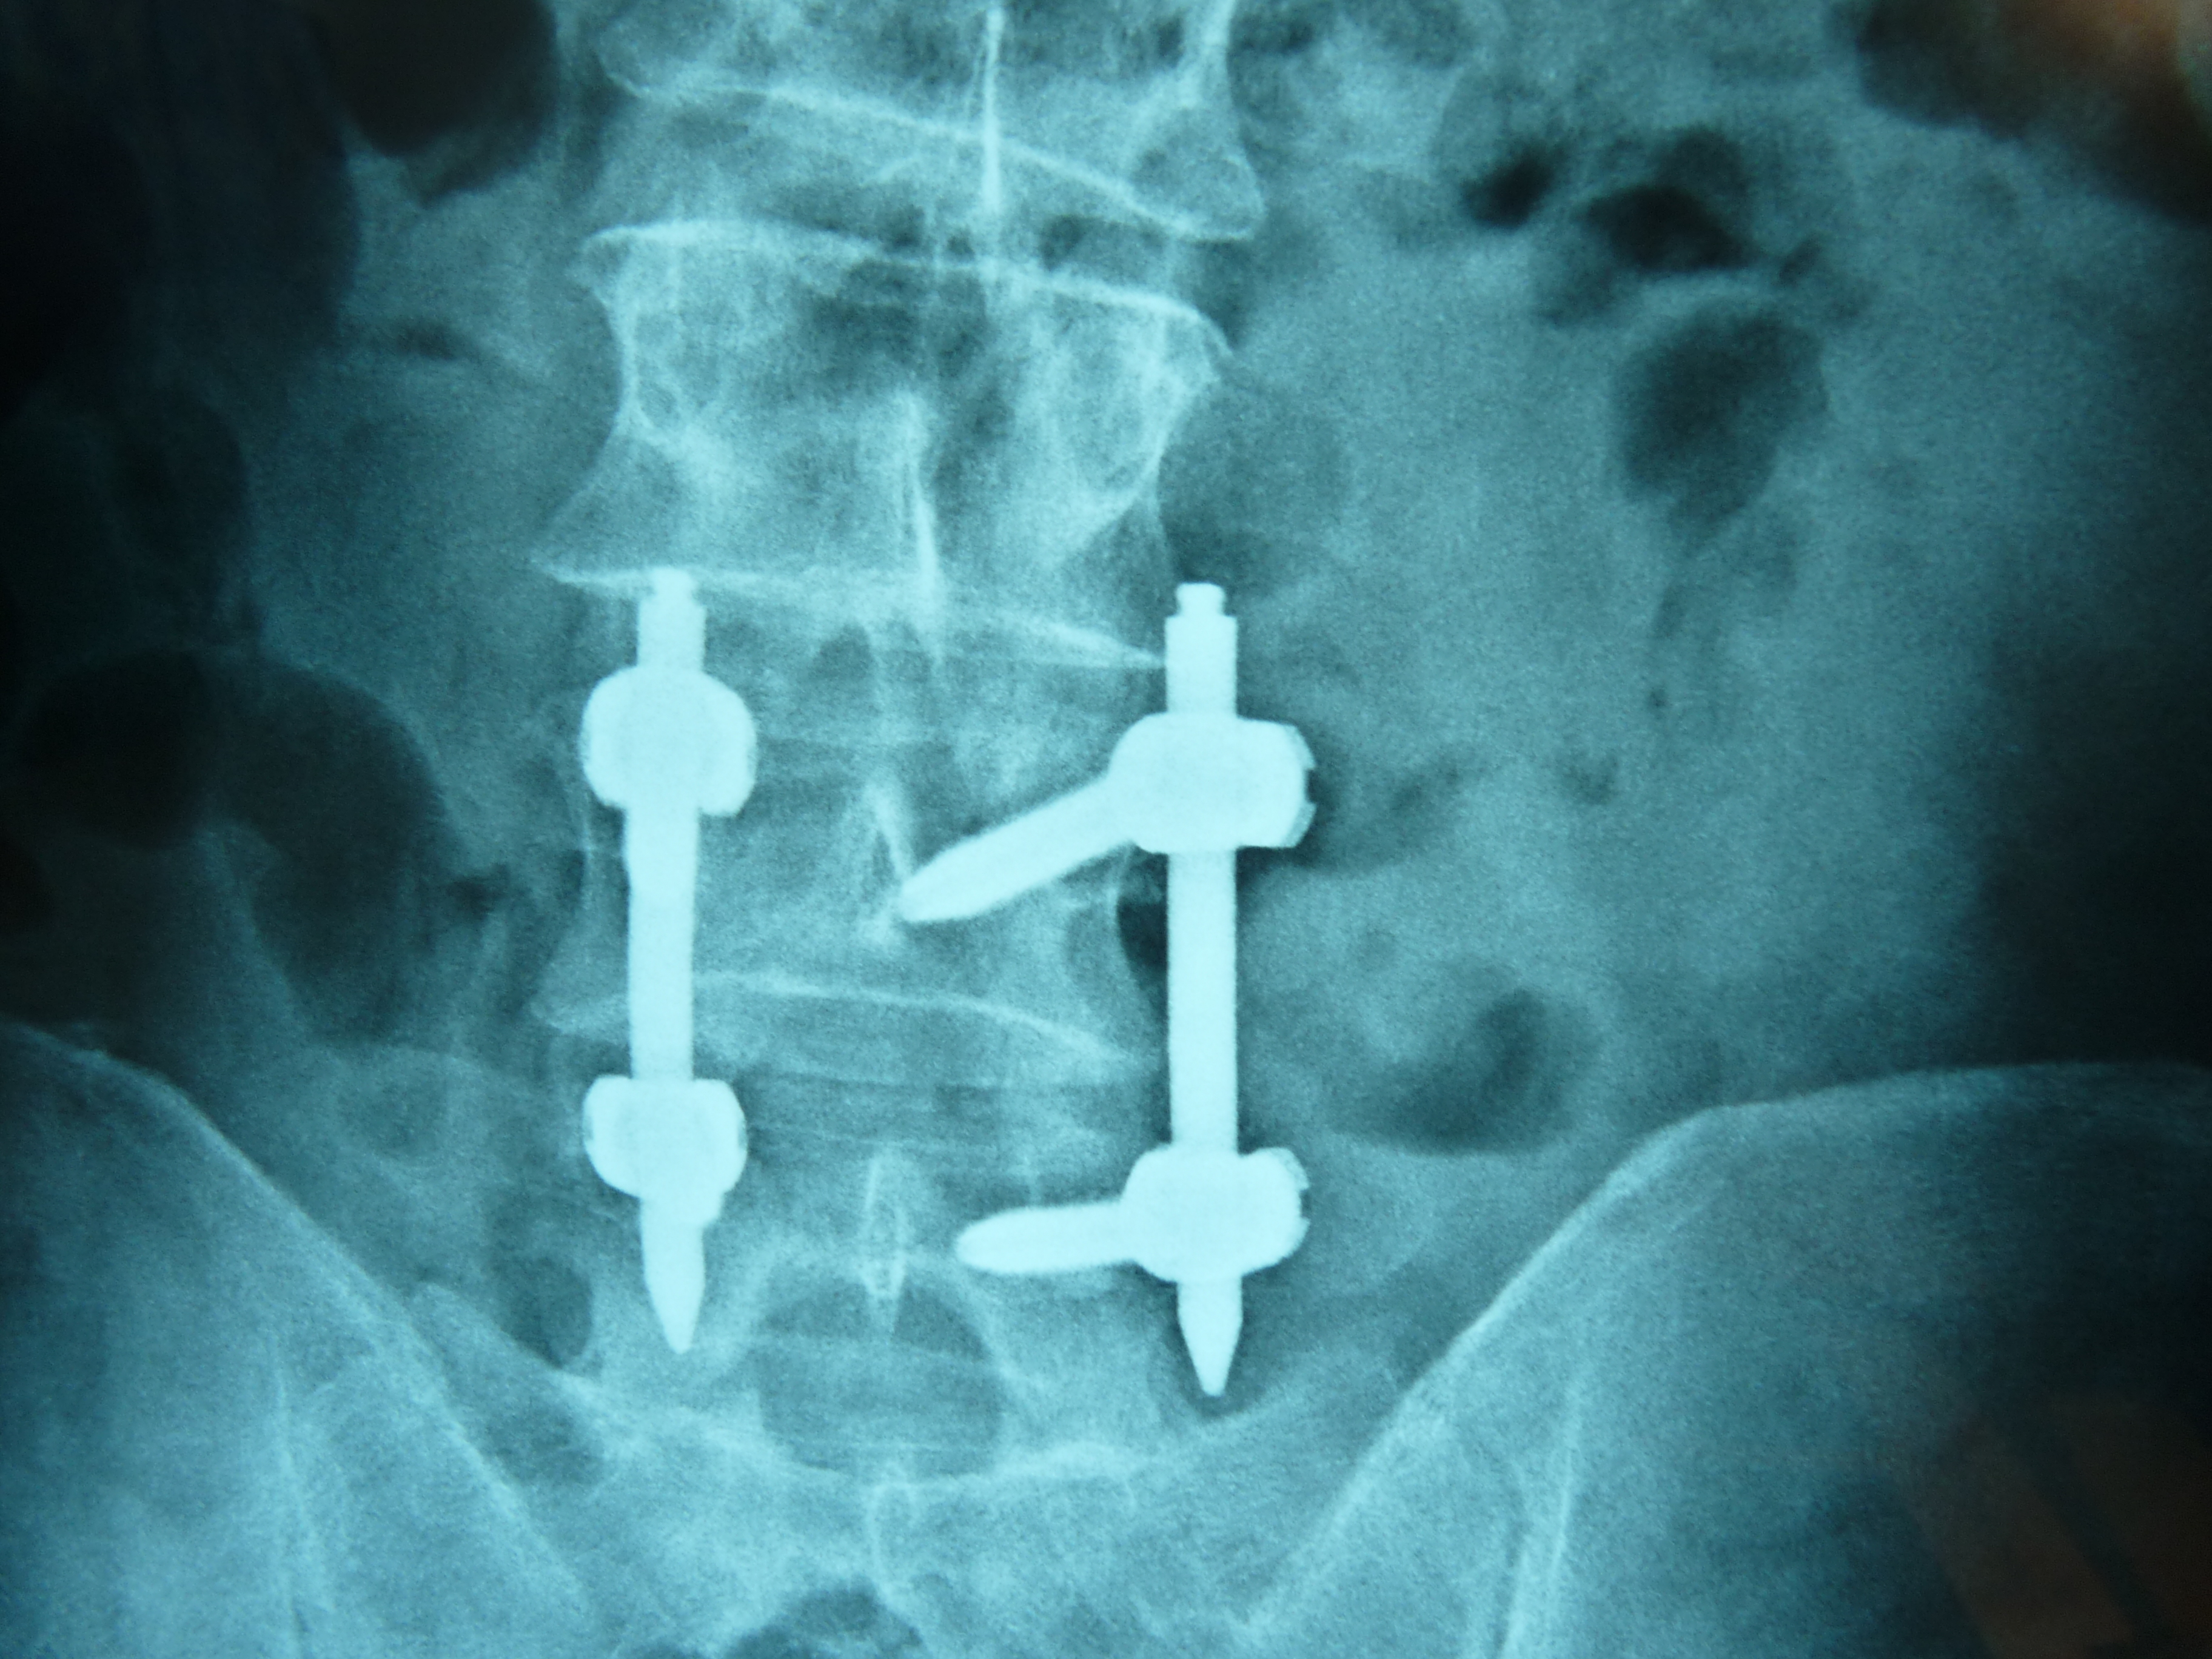

Εικόνα 4: Προσθιοπισθία (α) και πλαγία (β) μετεγχειριτική ακτινογραφία

Παρατηρούμε σταθεροποίηση της Ο.Μ.Σ.Σ. με το σύστημα κοχλιών – ράβδων